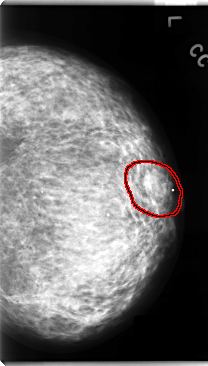

C_0130_1.LEFT_CC

LEFT_CC LINES 4752 PIXELS_PER_LINE 2704 BITS_PER_PIXEL 12 RESOLUTION 50 OVERLAY

FILE: C_0130_1.LEFT_CC.OVERLAY

TOTAL_ABNORMALITIES 1

ABNORMALITY 1

LESION_TYPE MASS SHAPE OVAL MARGINS ILL_DEFINED

ASSESSMENT 4

SUBTLETY 3

PATHOLOGY MALIGNANT

TOTAL_OUTLINES 1

BOUNDARY